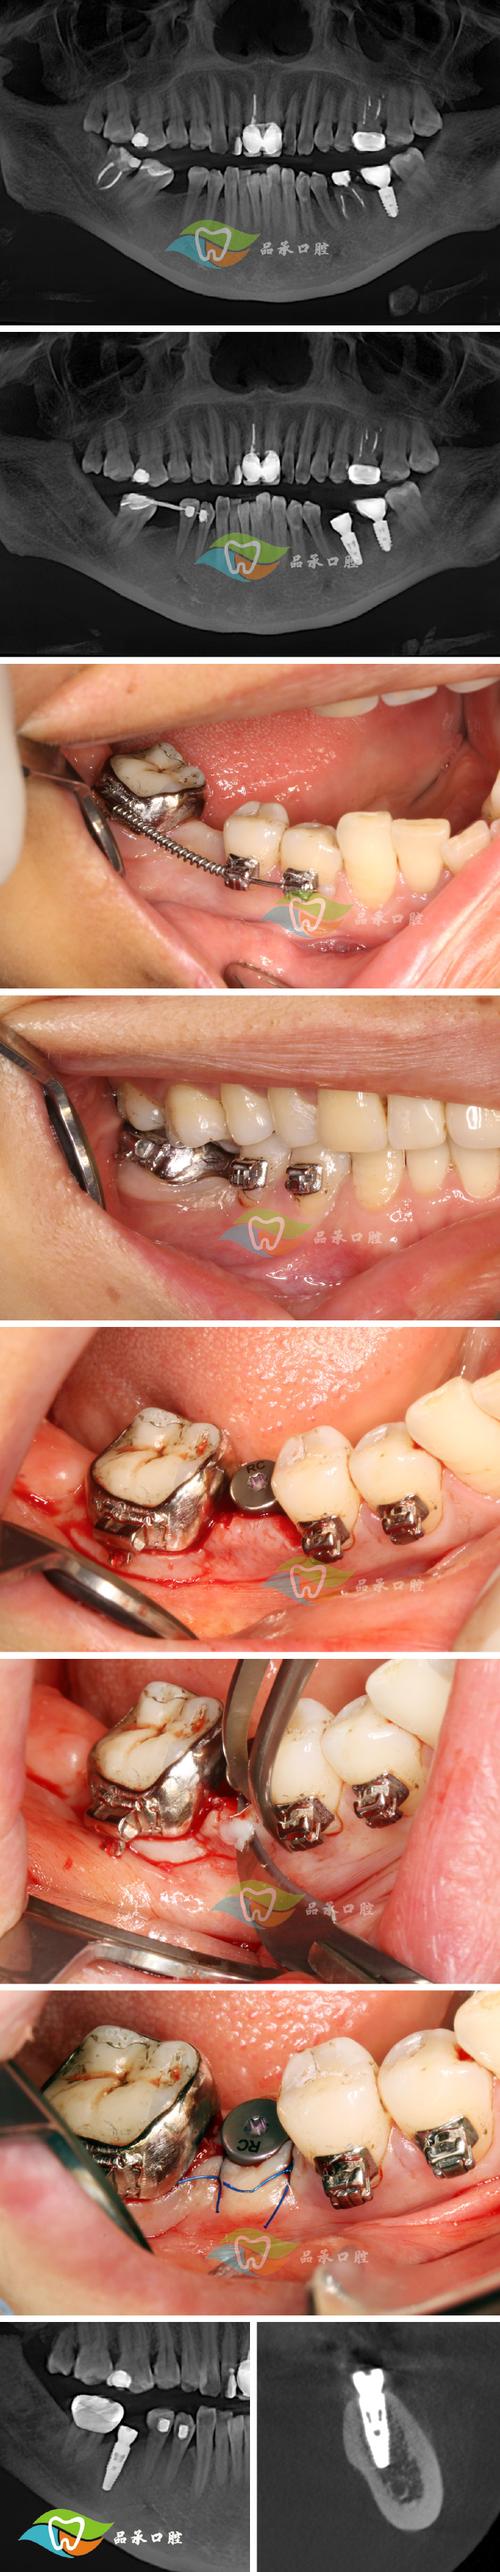

边缘粗糙或位置不当:

(图片来源网络,侵删)- 带环在制作或粘接过程中,如果边缘打磨不光滑,存在毛刺、锐边或不规则处,就会像小刀子一样不断摩擦娇嫩的口腔黏膜。

- 带环的位置如果略微偏离理想位置,或者牙齿在移动过程中改变了位置,都可能使带环边缘更贴近甚至压迫黏膜。

带环内部结构刺激:

带环内部通常焊接有颊面管(用于固定弓丝)或舌侧附件,这些附件的边缘如果处理不当,也可能刺激到对应位置的黏膜(如颊黏膜、舌侧)。